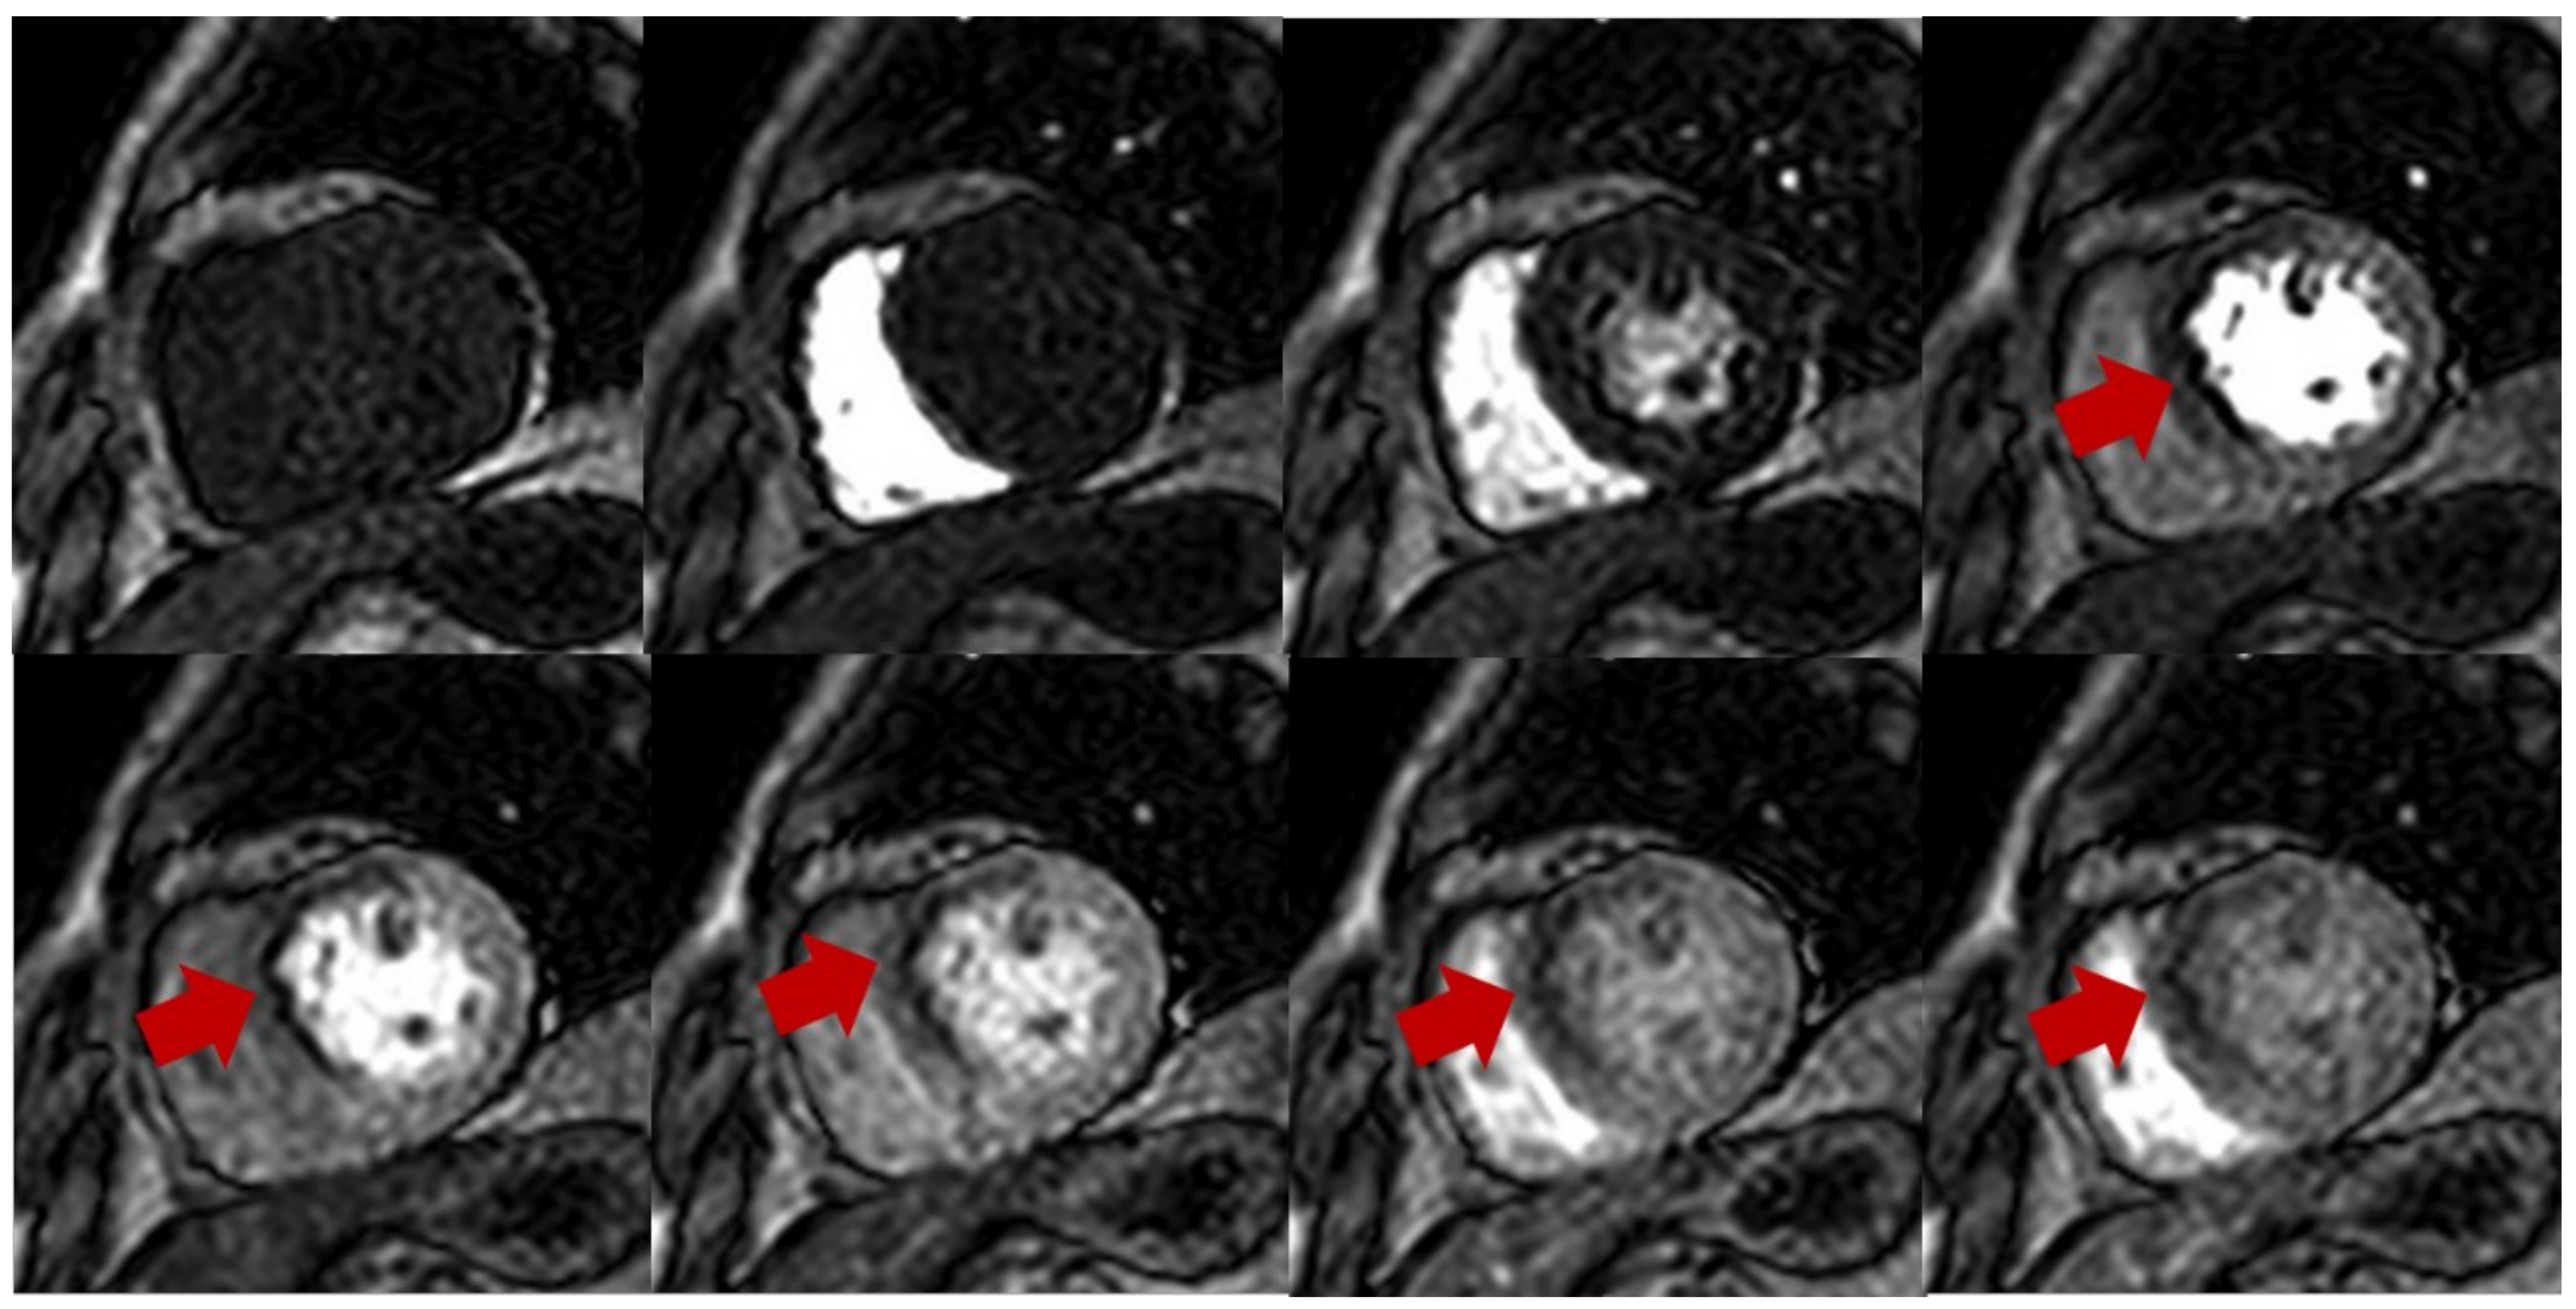

Figure 1.

Stress perfusion showing myocardial ischemia using adenosine. Upper and lower panel shows a single basal ventricular short axis slice acquired during stress perfusion imaging. The gadolinium contrast first enters the right ventricle, then the left ventricle, and finally perfuses the myocardium. Red arrow shows myocardial ischemia in the basal anteroseptal wall with decreased T1 signal compared with normal segments.